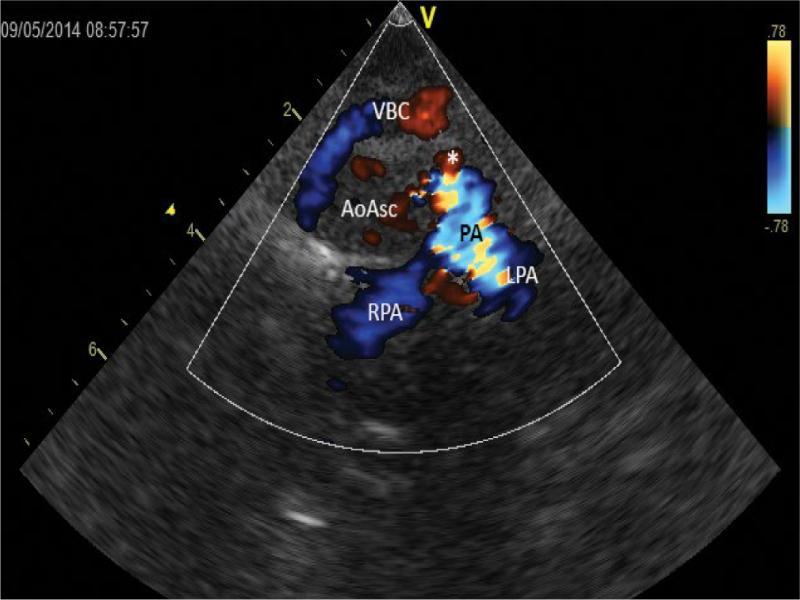

A slightly higher cross-section, diastole. The ascending aorta (AoAsc) is not filled with color. Despite the diastolic phase, the pulmonary trunk (PA) and its two branches (RPA and LPA) are filled with intensive blue color – with distinct turbulence. A bulge corresponding to the outlet of the ductus arteriosus (*) is seen in the anterior contour of the pulmonary trunk (PA). The left common carotid artery is not visible during this phase. VBC – the brachiocephalic vein

Echocardiographic diagnosis revealed situs solitus, compatible venoatrial and atrioventricular junctions; aortic dextroposition (40–50%) over a large (approx. 12 mm) perimembranous ventricular septal defect (VSD). There was a bidirectional ventricular septal defect shunt, with left-to-right predominance. Right-sided aortic arch. Due to difficult anatomical conditions, no conclusion was made regarding the morphology of arterial branches of the arch (Fig. 2, Fig. 3, Fig. 4. Fig. 5, Fig. 6, Fig. 7 and Fig. 8). Figure 2, Fig. 3, Fig. 4 and Fig. 5 show a series of upper mediastinal vessel sections in a plane similar to transverse plane – horizontal.